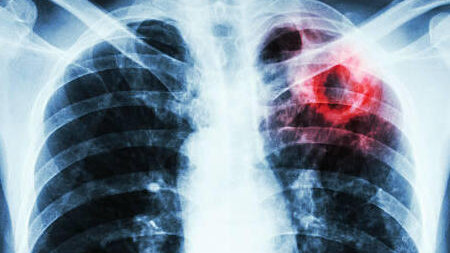

Первые признаки открытой формы туберкулеза, как обнаружить и как вылечиться?

Одной из самых распространенных инфекций в современном нам мире является туберкулез. Возбудителем этой патологии является палочка Коха. Ее опасность заключается в том, что заразиться можно воздушно-капельным путем, то есть при обычном контакте с человеком. Больной человек особенно опасен для других, если патология протекает в открытой форме, так как вместе с его мокротой выделяется большое количество микобактерий. Особенно опасна открытая форма туберкулеза для людей с низким иммунитетом. Туберкулез, при котором происходит постоянное выделение микобактерий во внешнюю среду, называется открытый...